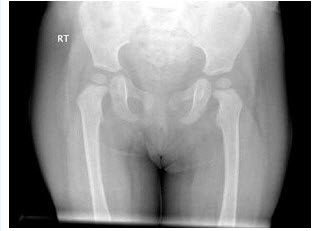

150、单项选择题

女,根据其正常骨盆影像图像,判断其最可能的年龄()

A.1岁左右

B.5岁左右

C.3岁左右

D.7岁左右

E.9岁左右